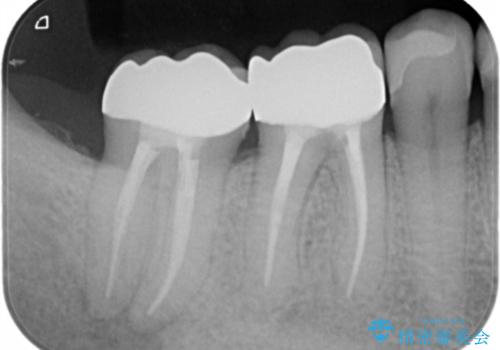

- 咬んだ時に右下奥歯に痛みがあるとの事で来院された患者様です。

歯の神経は壊死していたため、精密根管治療と補綴治療を計画しました。

セラミックでの治療を希望されたので補綴はオールセラミッククラウンでの治療を選択しました。

痛みは完全に取り除かれ、咬合時の違和感もなく経過は良好です。